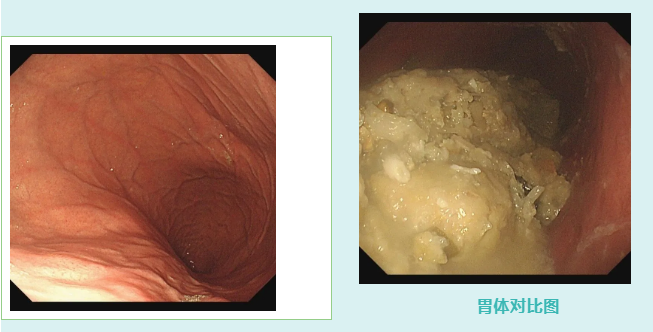

接诊的吕主任详细询问病史后,初步判断关女士可能因大量食用山楂引发了胃结石。随后的无痛胃镜检查证实了这一猜测——关女士的胃体里有一颗超大结石。

由于结石体积过大,无法直接通过内镜取出,吕主任建议她回家后通过饮用碳酸饮料配合药物治疗,尝试溶解结石。